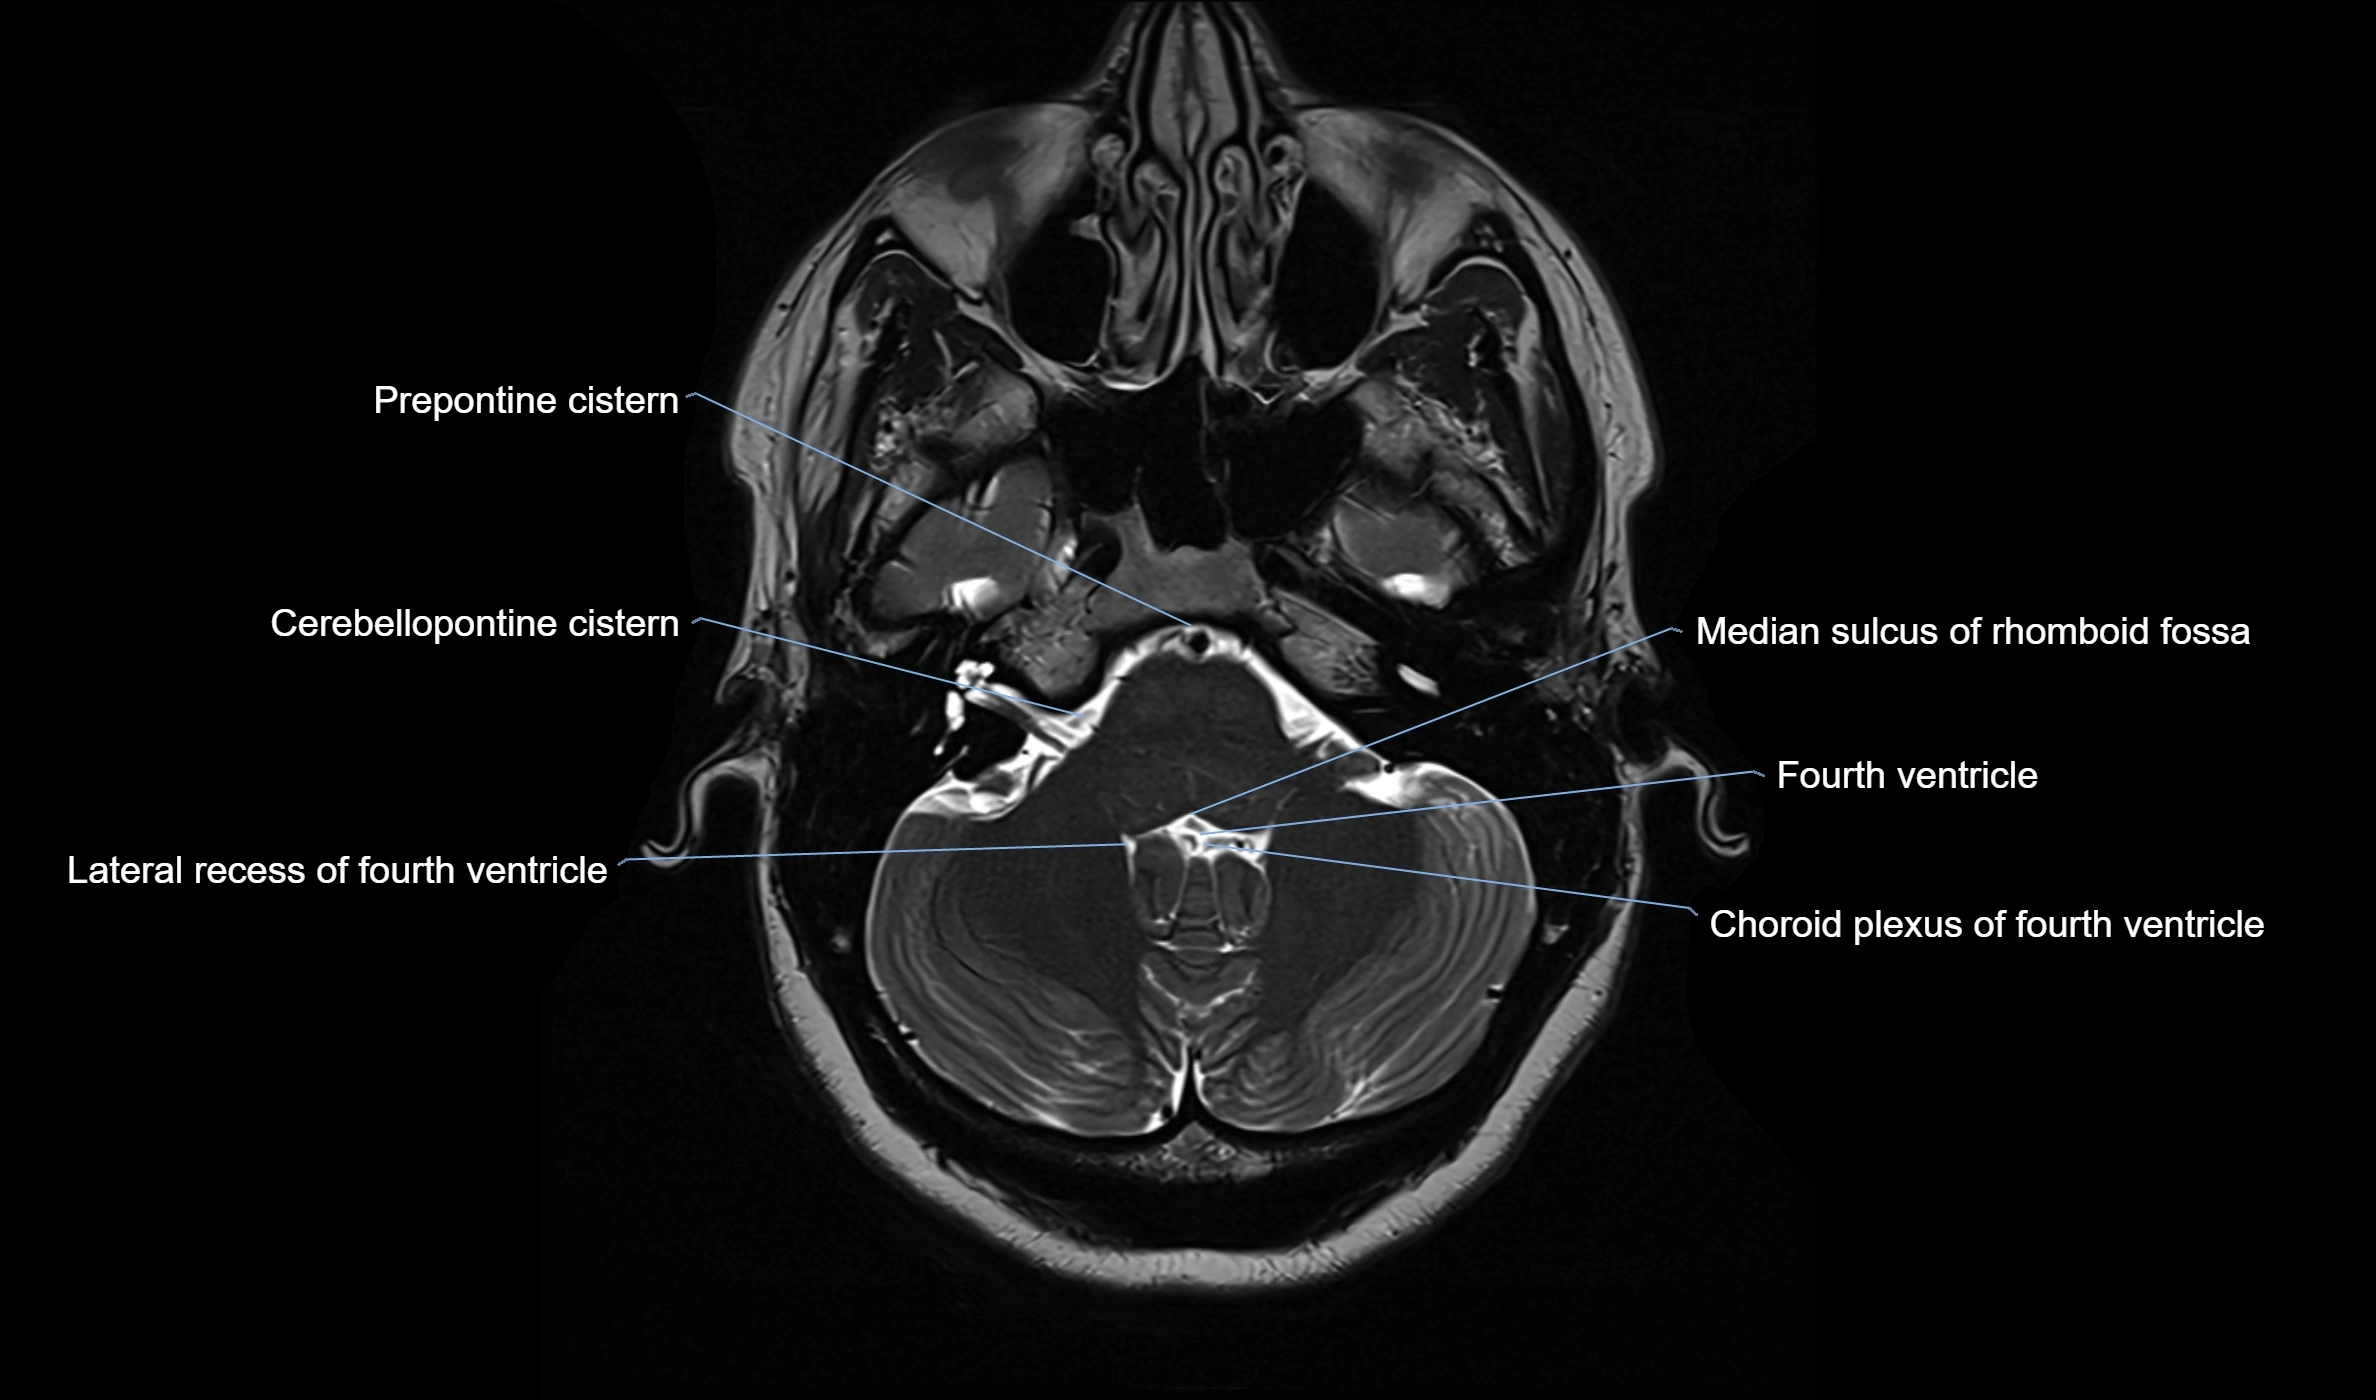

CT image

image